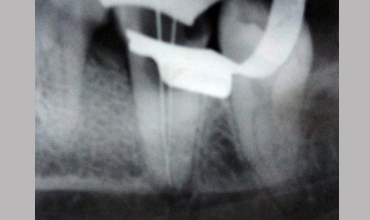

Management Of Single Root

Management Of Single Root With Single Canal In Mandibular Second Molar